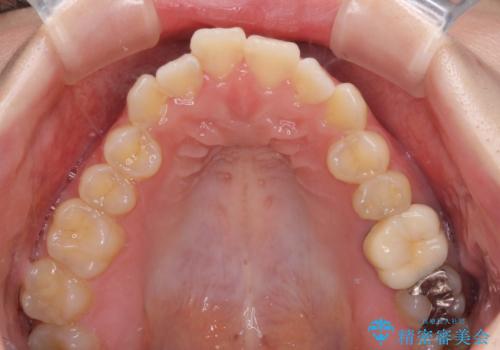

オープンバイトと前歯のデコボコをインビザライン矯正で解消

- 前歯の開咬を気にして来院された患者様です。

開咬の治療は、前歯を閉じるように動かすとともに、上下臼歯を圧下(骨内にめり込ませる)させることで進めて行きます。

インビザラインは臼歯の圧下を効果的に行えるため、インビザラインを用いて矯正治療を行うこととしました。